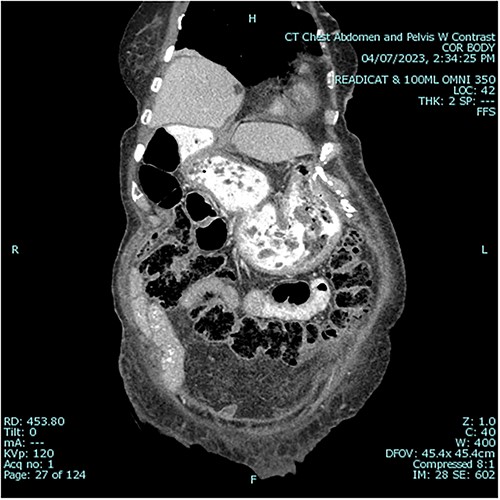

A 79 year old female patient presented to the emergency department with a two-day history of intractable nausea, vomiting, and diffuse abdominal pain. She reported having had a left groin bulge for 70 years and did not regularly see a doctor. Vital signs were notable for tachycardia and tachypnea. Physical exam was notable for a firm and distended diffusely-tender abdomen; and an associated giant incarcerated left inguinal hernia, extending down to the thigh. Laboratory evaluation revealed leukocytosis (WBC 20 K/uL), lactic acidosis (lactate 5 mmol/L), and acute kidney injury (Cr 1.5 mg/d). Computed tomography imaging demonstrated a giant left inguinal hernia containing the stomach, proximal duodenum, right hemicolon, and omentum, and associated free intraabdominal fluid and pneumoperitoneum (Fig 1). Aggressive intravenous fluid resuscitation, broad spectrum antibiotics, and vasopressor-support were started for septic shock secondary to perforated viscus. The patient was taken emergently to the OR for exploratory laparotomy. Operative findings included the following: left inguinal hernia containing the aforementioned structures, herniation of the stomach with severe gastric distension, a 0.5 cm diameter gastric perforation with surrounding necrosis at the mid portion of the lesser curve, and large volume ascites containing gastric contents. Operative interventions included the following: manual reduction of bowel and omentum from the left inguinal hernia sac, wedge resection of the perforated stomach (Figs 2 and 3), and abdominal washout. The patient was noted to have loss of abdominal domain due to the longstanding hernia. Her abdomen was closed using a biological mesh in a bridging fashion, as the fascia could not be closed primarily. Wide drainage was achieved using four 19Fr Blake drains. After surgery, the patient recovered from septic shock while being cared for in the intensive care unit. Her postoperative course was complicated by atrial fibrillation, pulmonary embolism, and COVID-19 infection. Discharge to a rehabilitation center occurred on hospital day 20. Follow up computed tomography imaging is as shown (Fig 4). Staged repair of the left inguinal hernia with permanent prosthetic mesh is planned in the near future.

Postoperative sagittal view, demonstrating stomach back in normal anatomical position1.